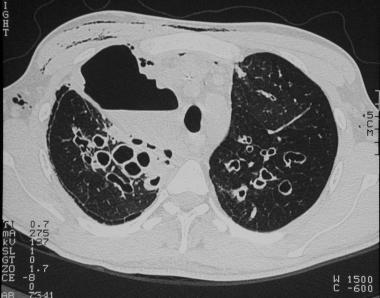

➢支气管扩张:支气管扩张是最常见的CT异常,约80%的患者可见支气管扩张,可见柱状型、曲张型和囊状型扩张。

图11 CF及急性胸痛患者的CT显示柱状型及囊状性支气管扩张,以及右上叶的空隙和皮下气肿。气胸是出现囊肿时的常见并发症。